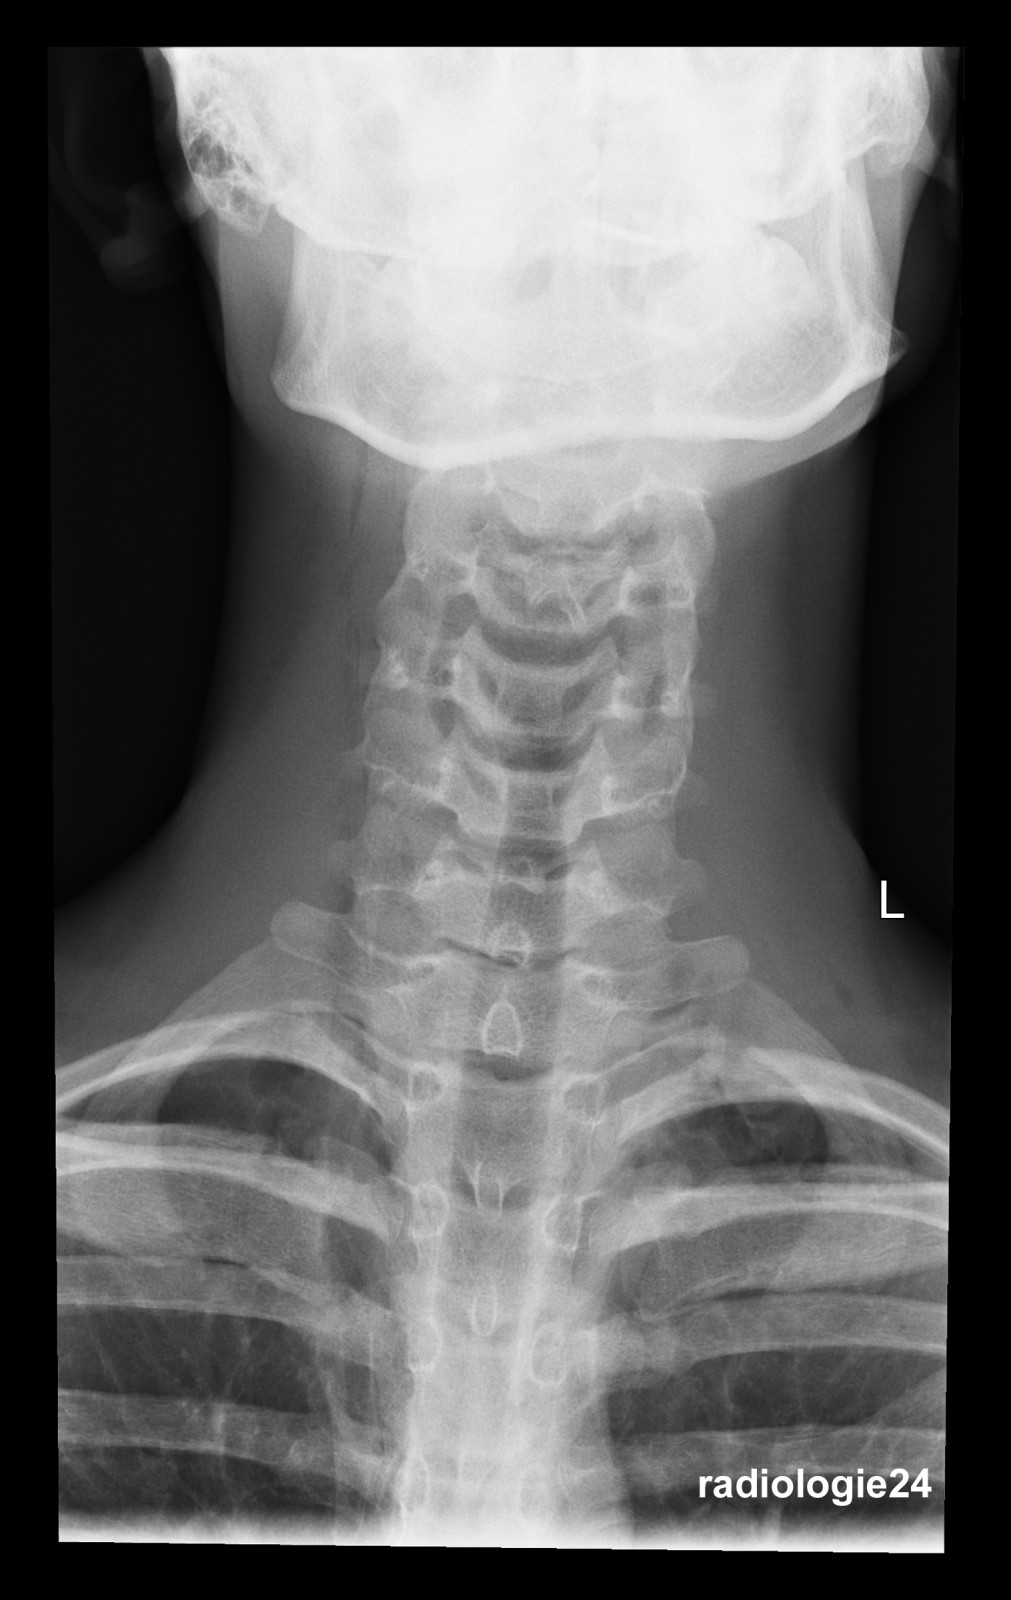

Röntgenfall des Monats Januar 2018 mit Auflösung

17 jähriger Patient Sturz auf den Rücken beim Crossbiken. Schmerzen HWS und Thorax. Fraktur, Pneumothorax, andere Pathologien? Weitere bildgebende Diagnostik? Welche? Warum?

Bild vergrössern

Link zur Auflösung mit ausführlichem Befund:

https://www.radiologie24.ch/radiologie-mediathek/roentgenfall_des_monats